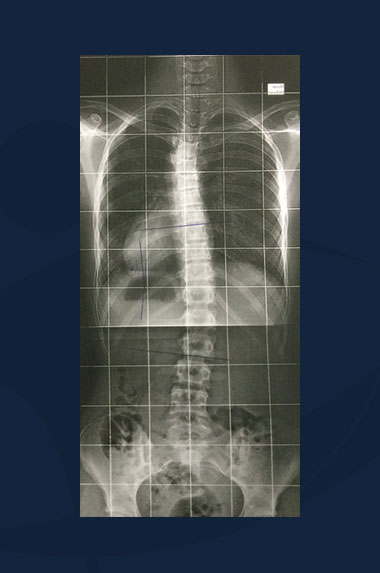

Mike Johnson

Clichés radiologiques du rachis (sans corset).

Scoliose Lombaire